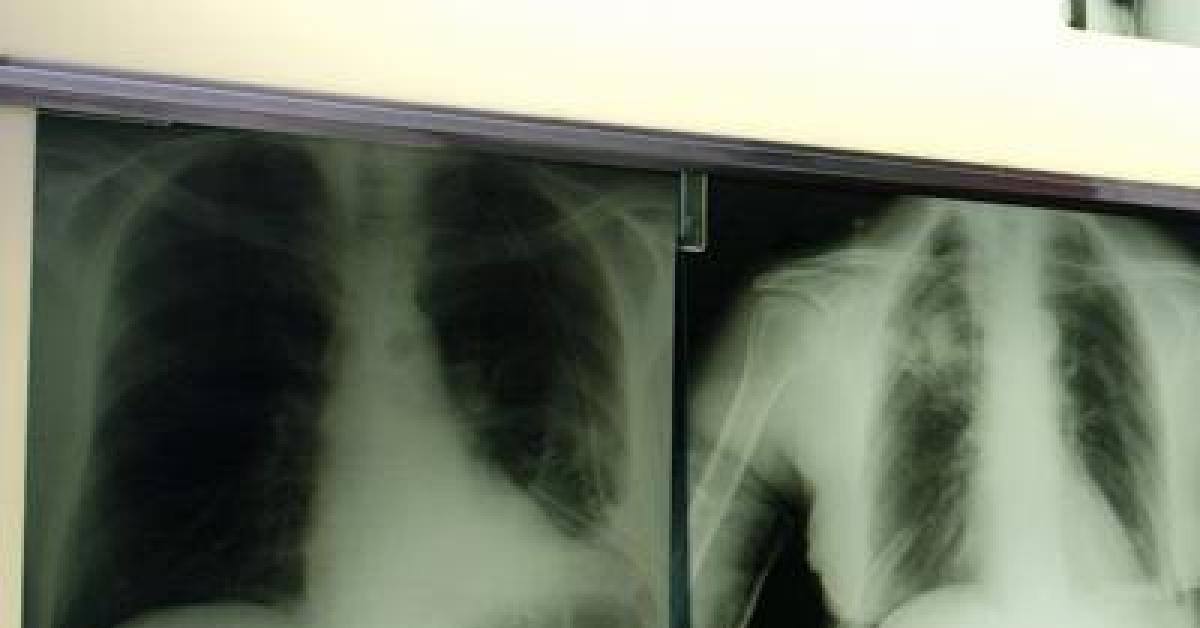

Roma, 7 ott. (Adnkronos Salute) - Ogni anno circa 290mila casi di infezione respiratoria acuta negli adulti e 1.800 decessi. Sono i numeri registrati solo in Italia per il virus respiratorio sinciziale (Vrs o Rsv nella sigla inglese), che si presenta con sintomi simil-influenzali, ma può determinare complicanze respiratorie significative nei soggetti fragili come over 60, persone immunocompromesse e neonati. Un fenomeno sottovalutato e sottostimato, specialmente nella popolazione adulta e anziana: spesso, infatti, la malattia da Rsv non viene diagnosticata correttamente. La protezione dei soggetti fragili resta la priorità: in Italia si registrano infatti oltre 50mila ricoveri all'anno. Nel dettaglio si calcano circa 25mila ospedalizzazioni di bambini sotto i 5 anni di età legate alle complicanze come bronchiolite e polmoniti, e circa 26mila negli over 60. Sul fronte della prevenzione, sono oggi disponibili strumenti sicuri ed efficaci come la vaccinazione e l'immunoprofilassi; nonostante queste opportunità, però, l'Rsv non è ancora incluso nel Piano nazionale di prevenzione vaccinale (Pnpv).

Il virus respiratorio sinciziale colpisce in modo diverso nelle differenti fasce d'età. L'Rsv "è un virus ubiquitario che colpisce praticamente tutti i bambini entro i 2 anni di vita, con possibili reinfezioni nel corso della prima infanzia e financo in età adulta - illustra Paolo Manzoni, professore associato di Pediatria e neonatologia, università di Torino – Se nei soggetti oltre i 2 anni di età il virus causa spesso sintomi simil-influenzali, colpendo per lo più le vie aeree superiori, al contrario una percentuale importante di pazienti con età meno di 2 anni presenta coinvolgimento delle basse vie aeree che può sfociare, nello specifico, nel quadro clinico classico conosciuto come bronchiolite e nelle sue complicanze sia immediate, sia a lungo termine". Oltre ai neonati prematuri e di età inferiore ai 6 mesi, le popolazioni a rischio di sviluppare una patologia respiratoria grave a seguito di Rsv sono le persone over 60 e quelle immunocompromesse o con patologie preesistenti come il diabete, le malattie cardiache e polmonari, nelle quali il virus può scendere alle vie respiratorie inferiori causando principalmente polmonite.